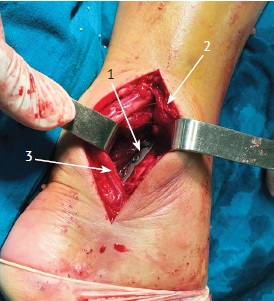

Пример использования методики представлен на рисунке 3.

Рис. 3. Хирургическое лечение пациентки с переломом типа 44С2.3:

а, b — первичные рентгенограммы в прямой и боковой проекциях;

c, d, e, f — данные КТ, показывающие размер заднего края ББК;

g, h — послеоперационные рентгенограммы в прямой и боковой проекциях — анатомичная репозиция костных отломков в области голеностопного сустава;

i, j — функциональный результат лечения через 48 нед. после травмы

Fig. 3. Surgical treatment of a patient with a fracture 44C2.3:

a, b — primary X-rays in AP and lateral projections;

c, d, e, f — CT data showing the size of the posterior edge of the tibia;

g, h — postoperative X-rays in AP and lateral projections — anatomical reposition of bone fragments in the ankle joint;

i, j — functional result of treatment 48 weeks after injury